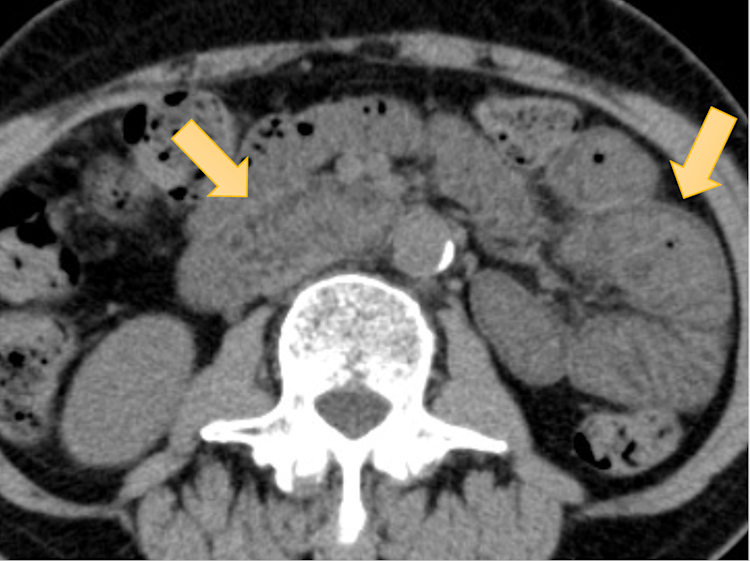

マルチキナーゼ阻害薬であるレンバチニブ(レンビマ®)による腸炎のCT所見や消化器系合併症(下痢、食思不振、嘔気、嘔吐)や治療方針への影響を検討した論文です。レンバチニブは切除不能な肝細胞癌や切除不能な甲状腺癌に対して近年使用されるようになり、高い治療効果が報告されていますが、一方で合併症によって休薬や治療中止を余儀なくされる症例も高頻度であることが知られていました。本研究では、背景の悪性腫瘍の種類にかかわらず高頻度でCTで小腸炎様の所見を呈することや、この所見が認められた症例では休薬に追い込まれる頻度が有意に高いことなどを示しました。レンバチニブで高頻度に生じることが知られている消化器系合併症は、実はsubclinicalな腸炎が原因となっているのかもしれない、とも考えています。